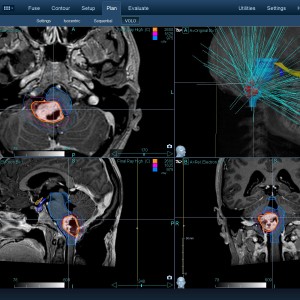

Στις παρακάτω φωτογραφίες θα δείτε παραδείγματα πλάνων θεραπείας καρκινικών όγκων με CyberKnife. Παρατηρήστε πόσο κοντά στους υγιείς ιστούς βρίσκονται οι καρκινικοί όγκοι που χρειάζεται να ακτινοβοληθούν. Μόνο με το CyberKnife και το προσωπικό πλάνο θεραπείας, μπορούν να ακτινοβοληθούν οι όγκοι χωρίς να πληγούν οι παρακείμενοι υγιείς ιστοί.

Μόνο με το CyberKnife και την κατάλληλη σχεδίαση της θεραπείας από έμπειρο νευροχειρουργό, μπορεί να ακτινοβοληθούν οι όγκοι χωρίς να επηρεαστούν από την ακτινοβολία οι υγιείς ιστοί. Αυτό εξασφαλίζει τη μέγιστη δυνατή απόδοση της ακτινοχειρουργικής θεραπείας των όγκων.

Με κόκκινο χρώμα περιγράφεται η περιοχή του όγκου.

Με μπλε, κίτρινο και πράσινο χρώμα περιγράφονται οι υγιείς ιστοί που δεν πρέπει να ακτινοβοληθούν.

Παρατηρήστε πόσο κοντά βρίσκεται ο όγκος με τους υγιείς ιστούς.

Παρατηρήστε τις πάρα πολλές δέσμες του CynerKnife που ακτινοβολούν τους όγκους από διαφορετικές γωνίες ώστε να μην προσβληθούν από την ακτινοβολία οι υγιείς ιστούς.